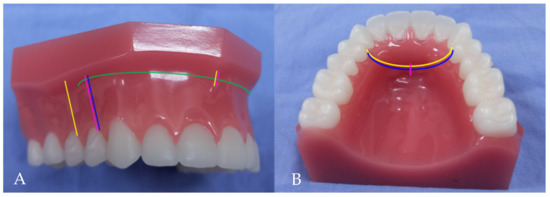

Patients with BiP treated at the Department of Oral and Maxillofacial Surgery of Kaohsiung Medical University were recruited if they (1) had no significant lip deformation before surgery and (2) had no history of abnormal facial development or facial trauma. Thirty-three patients were enrolled, aged 16 to 43 years, with a mean age of 27.5 years. Each participant underwent modified AMSO (Yellow line in the Figure 1A,B).

Figure 1.

Four different anterior maxillary subapical osteotomies (AMSO). Yellow line: present study (Modified AMSO); Green line: Cupar method; Blue line: Wunderer method; Pink line: Wassmund method. (A) Vestibular incisions (B) Palatal mucosal incisions.